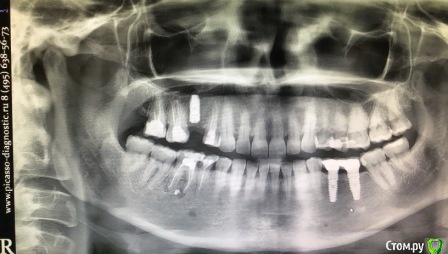

Tatiana72 Опубликовано 27 октября, 2020 Автор Поделиться Опубликовано 27 октября, 2020 Добрый вечер!Выкладываю скрины срезов Ссылка на исследованиеhttps://yadi.sk/d/ViQR0U6R2QjHzg Ссылка на комментарий

Дмитрий М Опубликовано 28 октября, 2020 Поделиться Опубликовано 28 октября, 2020 Добрый вечер!Выкладываю скрины срезовImage4.jpgImage5.jpgImage9.jpg Ссылка на исследованиеhttps://yadi.sk/d/ViQR0U6R2QjHzg не волнуйтесь всё хорошо, по КТ корень зуба не задетесть небольшой очаг разряжения на одном из апексов, обратитесь к стоматологу 1 Ссылка на комментарий